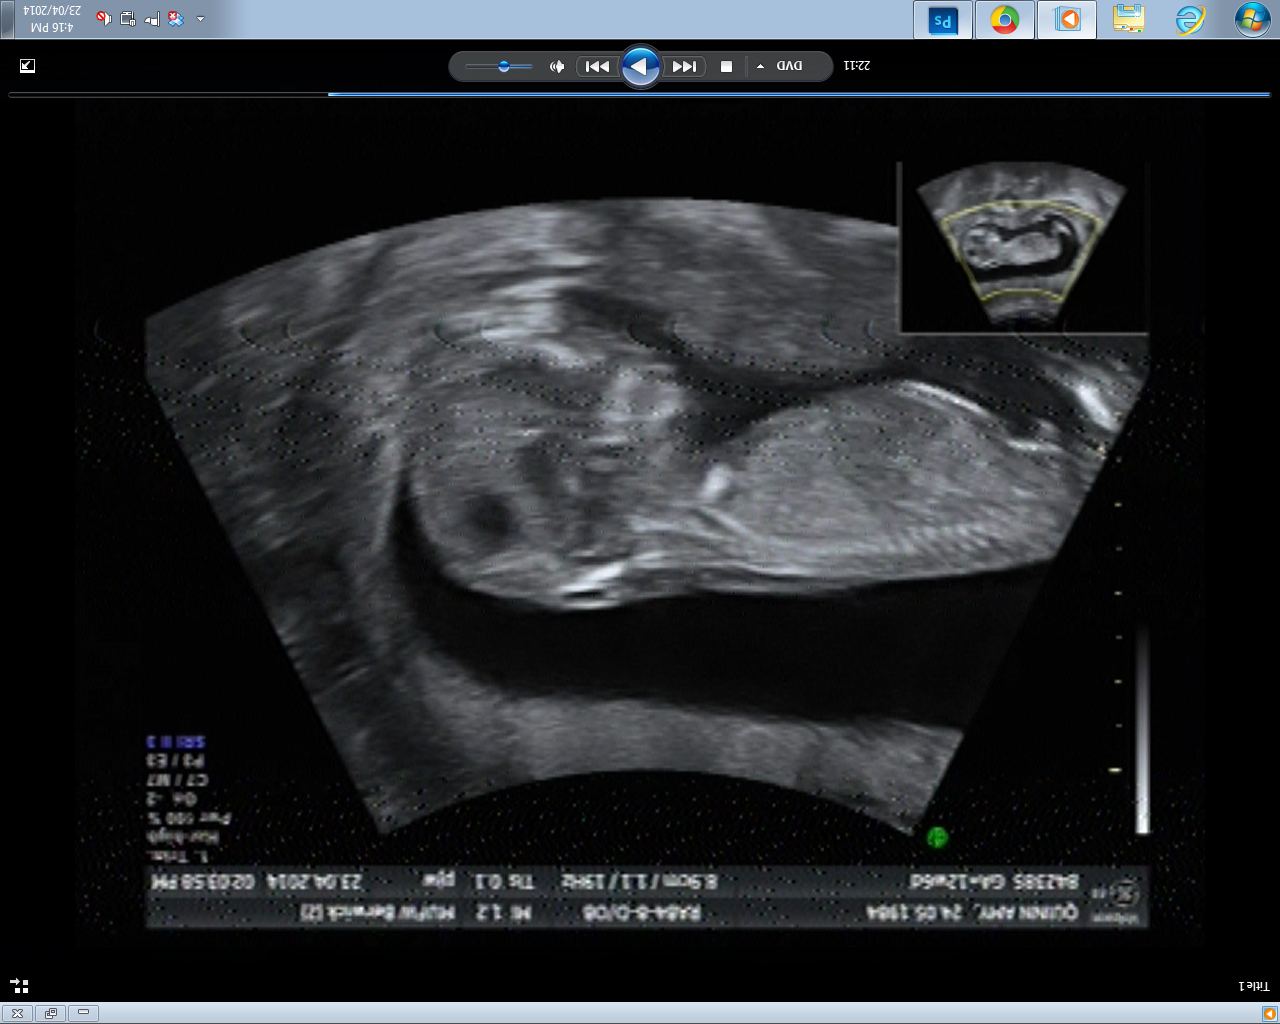

Three nub shots I was able to get, pulled off the DVD. I really didn't have much to work with - in 30 minutes of footage, these were the ONLY clear(ish) nub shots the whole time.

Attachment 18363Attachment 18364Attachment 18365